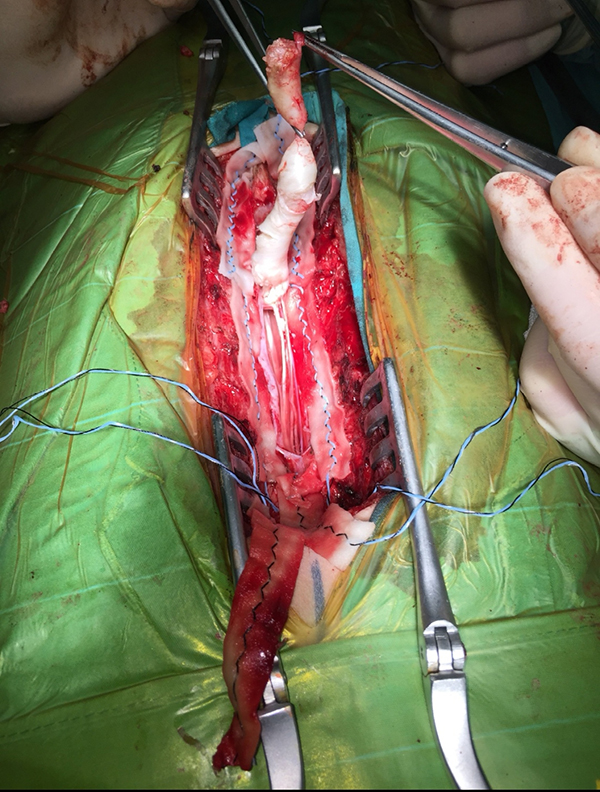

手术中正在从脊髓及神经上分离囊肿。(白色条状物)

完整切除的囊肿。